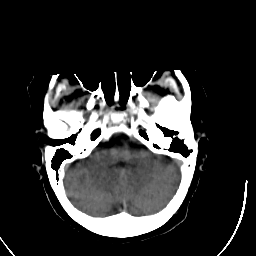

Stroke CT #3 -- Slice #4

[Home][Help][Clinical] Slice 4